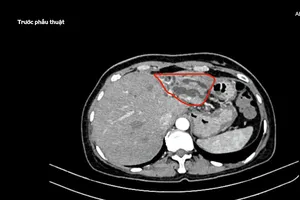

Ngày 8-4, Bệnh viện Quân y 175, TP.HCM, cho biết nơi đây vừa thực hiện thành công ca lấy ghép tạng từ người hiến chết não đầu tiên tại bệnh viện.

Người hiến tạng là ông NTT (sinh năm 1975), được chẩn đoán chết não do đột quỵ xuất huyết não diện rộng, biến chứng phù não nặng.

ca lấy ghép tạng từ người hiến chết não

Bệnh viện Quân y 175 phối hợp thực hiện thành công ca lấy ghép tạng từ người hiến chết não đầu tiên. Ảnh: BVCC